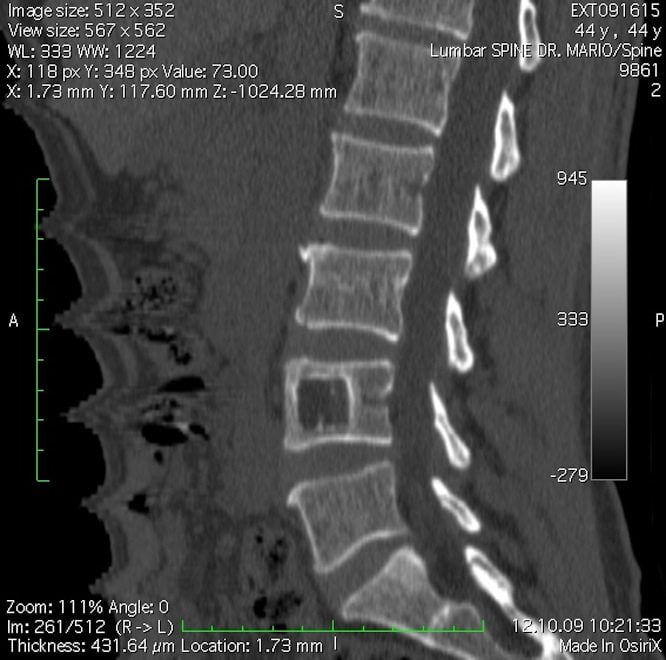

- ренгтенография позвоночника. Информативна в диагностике последних стадий остеохондроза. На рентгенограммах можно увидеть изменение расстояния между позвонками и разрастание остеофитов;

- МРТ позвоночного столба. Методика позволяет выявить практические любые патологические изменения позвонков, межпозвонковых дисков и суставов. Магнитно-резонансная томография позволяет выявить остеохондроз и спондилоартроз даже на начальных стадиях;

- миелография. Суть исследования заключается в рентгенконтрастном исследовании позвоночника. Метод позволяет выявить асбцессы, опухоли, сужение позвоночного канала, грыжи и разрывы межпозвоночных дисков;